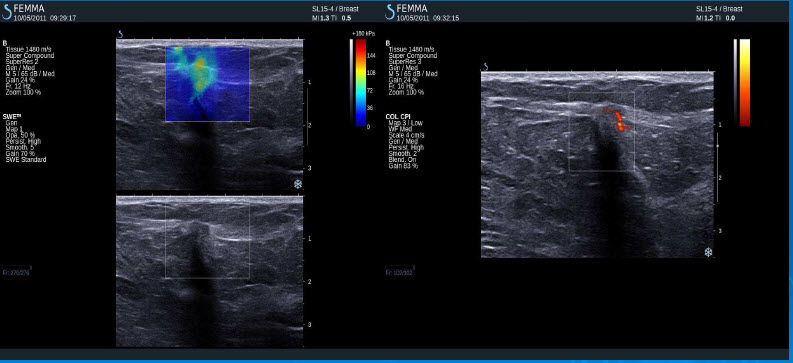

Negativní výsledky elastografie / histologicky potvrzená malignita

Mucinozní adenokarcinom